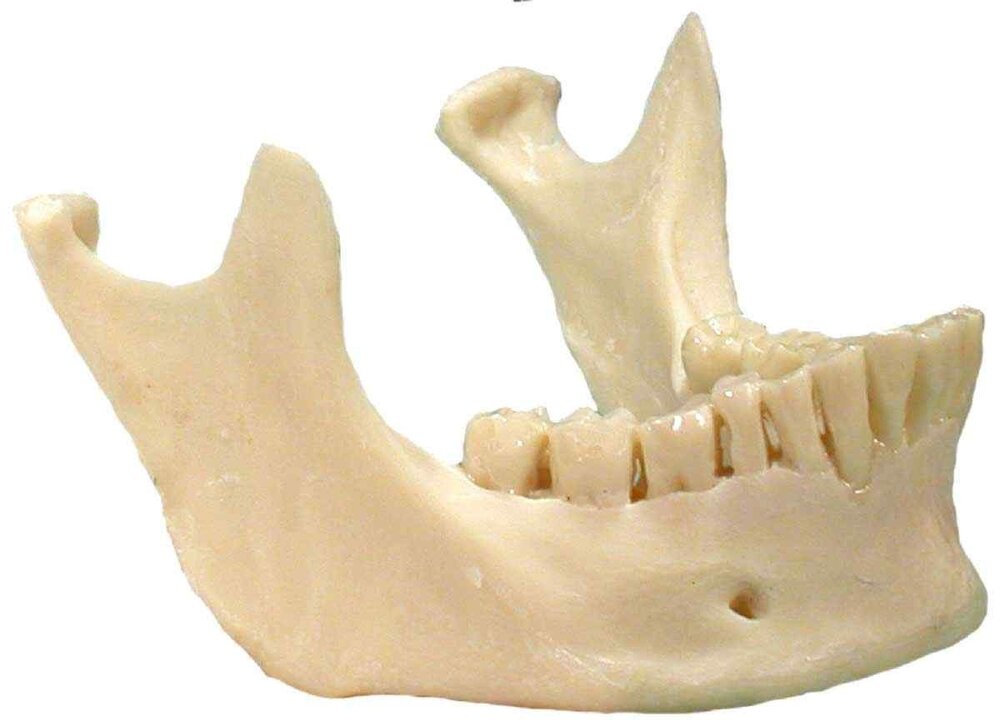

4. MSE + Facepulling *

11. Jaw surgery (Chin wing, BSSO, Bimax..)

12. Surgery on midface (Lefort 1-2, 3.. Midface lift, high cut lf1)

24. Chin wing osteotomy

11. Jaw surgery (Chin wing, BSSO, Bimax..)

12. Surgery on midface (Lefort 1-2, 3.. Midface lift, high cut lf1)

24. Chin wing osteotomy